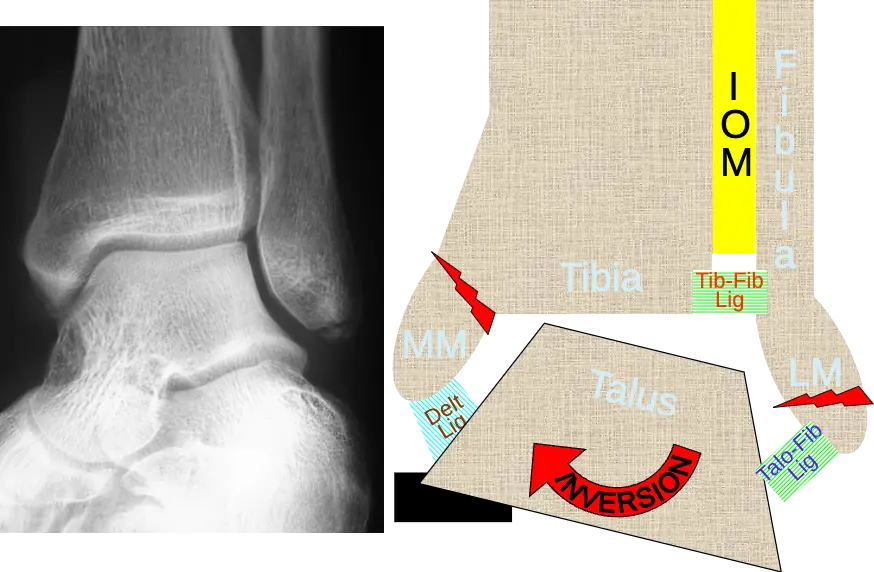

Mechanism of injury

- Mechanism of injury:

- Position of the foot at time of injury

- Magnitude, direction, and rate of loading